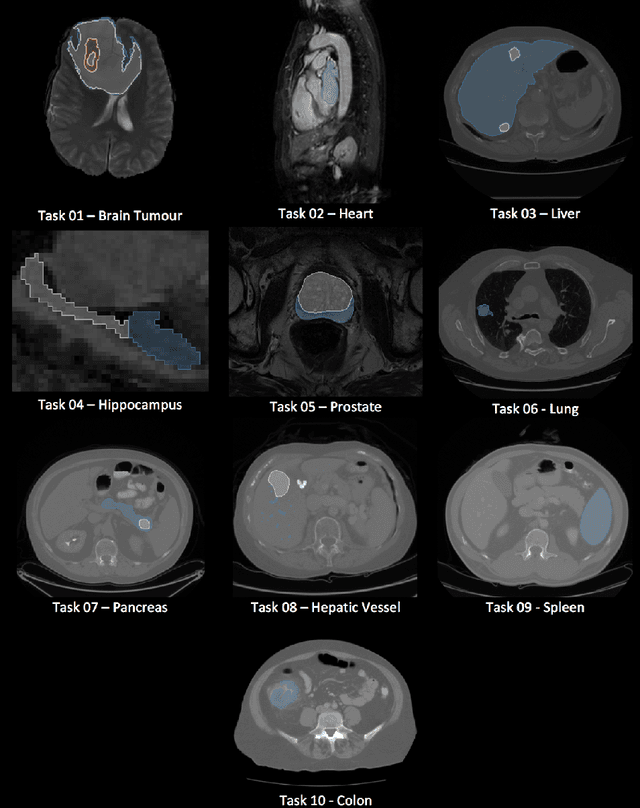

Abstract:International challenges have become the de facto standard for comparative assessment of image analysis algorithms given a specific task. Segmentation is so far the most widely investigated medical image processing task, but the various segmentation challenges have typically been organized in isolation, such that algorithm development was driven by the need to tackle a single specific clinical problem. We hypothesized that a method capable of performing well on multiple tasks will generalize well to a previously unseen task and potentially outperform a custom-designed solution. To investigate the hypothesis, we organized the Medical Segmentation Decathlon (MSD) - a biomedical image analysis challenge, in which algorithms compete in a multitude of both tasks and modalities. The underlying data set was designed to explore the axis of difficulties typically encountered when dealing with medical images, such as small data sets, unbalanced labels, multi-site data and small objects. The MSD challenge confirmed that algorithms with a consistent good performance on a set of tasks preserved their good average performance on a different set of previously unseen tasks. Moreover, by monitoring the MSD winner for two years, we found that this algorithm continued generalizing well to a wide range of other clinical problems, further confirming our hypothesis. Three main conclusions can be drawn from this study: (1) state-of-the-art image segmentation algorithms are mature, accurate, and generalize well when retrained on unseen tasks; (2) consistent algorithmic performance across multiple tasks is a strong surrogate of algorithmic generalizability; (3) the training of accurate AI segmentation models is now commoditized to non AI experts.

Abstract:Semantic segmentation of medical images aims to associate a pixel with a label in a medical image without human initialization. The success of semantic segmentation algorithms is contingent on the availability of high-quality imaging data with corresponding labels provided by experts. We sought to create a large collection of annotated medical image datasets of various clinically relevant anatomies available under open source license to facilitate the development of semantic segmentation algorithms. Such a resource would allow: 1) objective assessment of general-purpose segmentation methods through comprehensive benchmarking and 2) open and free access to medical image data for any researcher interested in the problem domain. Through a multi-institutional effort, we generated a large, curated dataset representative of several highly variable segmentation tasks that was used in a crowd-sourced challenge - the Medical Segmentation Decathlon held during the 2018 Medical Image Computing and Computer Aided Interventions Conference in Granada, Spain. Here, we describe these ten labeled image datasets so that these data may be effectively reused by the research community.